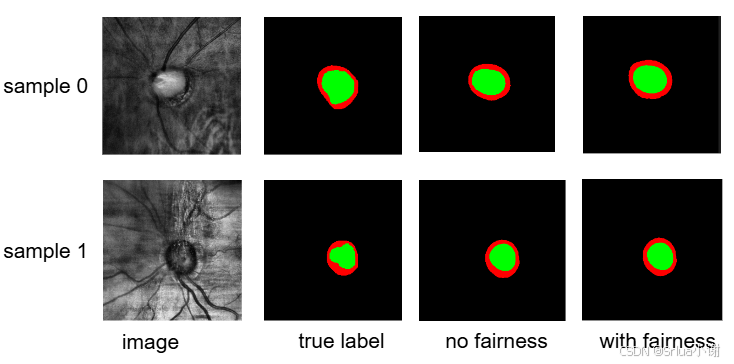

如上,sample 0和sample 1分别对应gender为0或1的情况,右侧三列的图分别展示了true label(真实label), no fairness(无公平性), with fairness(有公平性)的可视化情形。

我们按照原论文里的实验设置在HarvardFairseg上动手复现了实验结果,模型使用的是SAMed(vit-b), 敏感属性设置的是 性别(gender)。使用的batch size是42,learning rate是0.005, momentum 和 weight decay分别是0.9和0.1。

以下展现了训练好的实验模型在测试集上的结果。

这里与原论文repo的结果有一些差异(比如在Cup视杯上,加入公平性的SAMed的表现优于一般的SAMed,但是在Rim上与预期不符合)我们也在思考原因,欢迎在评论区讨论!